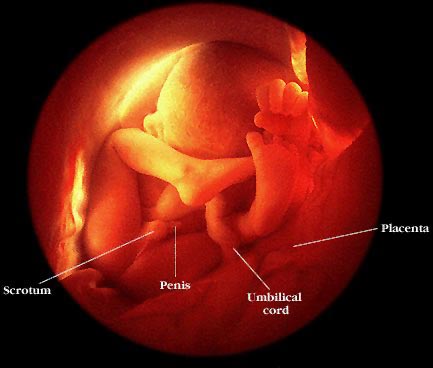

معرفة جنس الجنين:

بحلول الأسبوع الرابع عشر تكون أعضاء الطفل التناسلية قد تكونت بالكامل، ويكون بالإمكان معرفة جنس الطفل (ذكر أم أنثى) بالفحص بالموجات فوق الصوتية